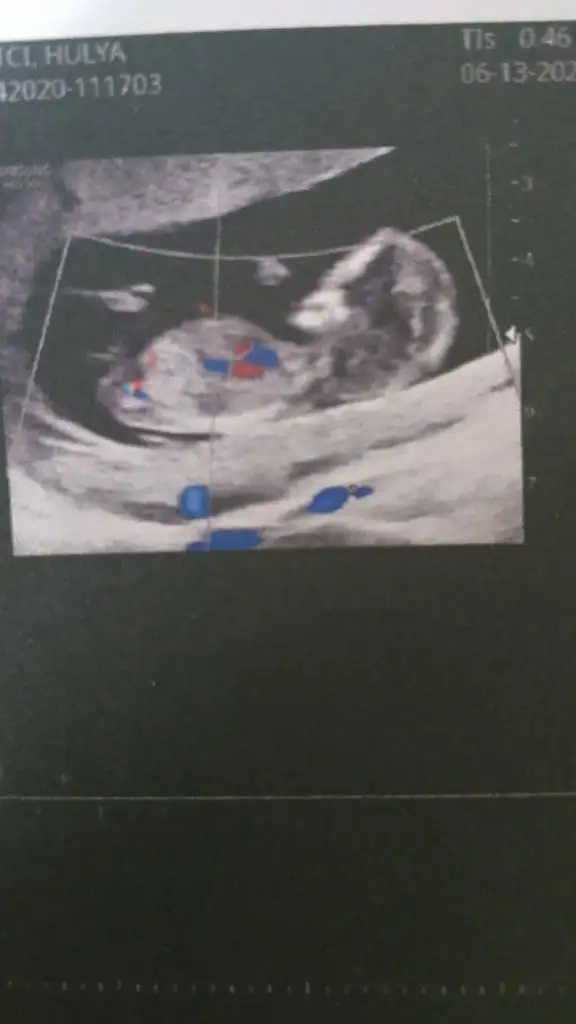

Kız gibi geldi nubu tam karşıya bakıyor ama ben oyumu kıza kullandım

Allah'ım ağzın bal yesin kızKız gibi geldi nubu tam karşıya bakıyor ama ben oyumu kıza kullandım

Hayırlısı olsun cnmAllah'ım ağzın bal yesin kızsen ne dersen tutuyor zaten gerçi kız olsun erkek olsun önemli değil sağlıklı olsunda ilk bebeğim erkek olunca gönlümde de kız yatmıyor değildi hani doktor söylemedi 2 hafta sonra gel bidaha bakalım dedi bakalım

Ay hadi İnşallah bakalım hayırlısı Rabbimdenben de ki diyorum benim usg ye benziyor inşallah kızdır ikimizin kide canımsonbuse